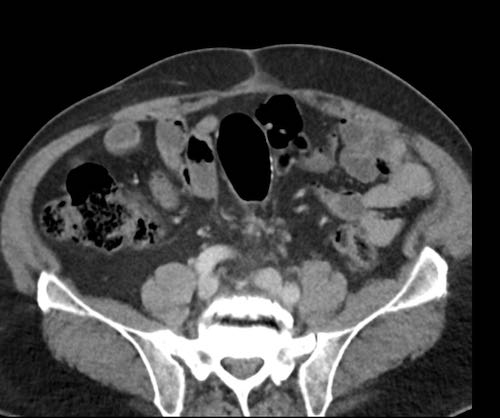

Cuộn xem ảnh CT

Ca lâm sàng 1

Cuộn qua các lát cắt.

Bạn có thể phát hiện tất cả các tổn thương cấy ghép phúc mạc không?

Bệnh nhân này đã được phẫu thuật và toàn bộ phúc mạc được ghi nhận phủ kín bởi các tổn thương u dạng kê.